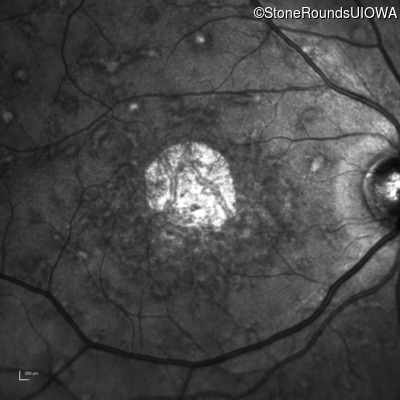

Age at visit: 52 years

This 52 year old man first noticed reduced visual acuity at age 21.

Age at visit: 54 years

Age at visit: 59 years